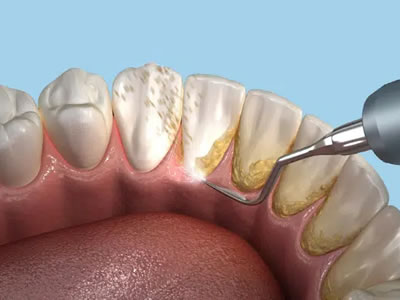

Tooth Extractions

Teeth cleaning and teeth whitening are two types of dental procedures that confuse patients.  The main objective of teeth whitening is to remove stains for cosmetic purposes.